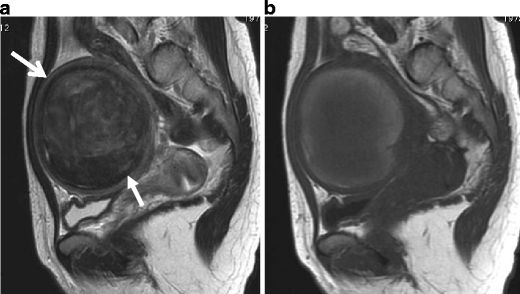

Red degeneration in a 36-year-old woman. a Sagittal T2-weighted image demonstrates a well-defined myometrial mass of low intensity, associated with thick rim of distinct low signal intensity (arrows). b T1-weighted image reveals entirely increased intensity in the tumor, suggesting red degeneration